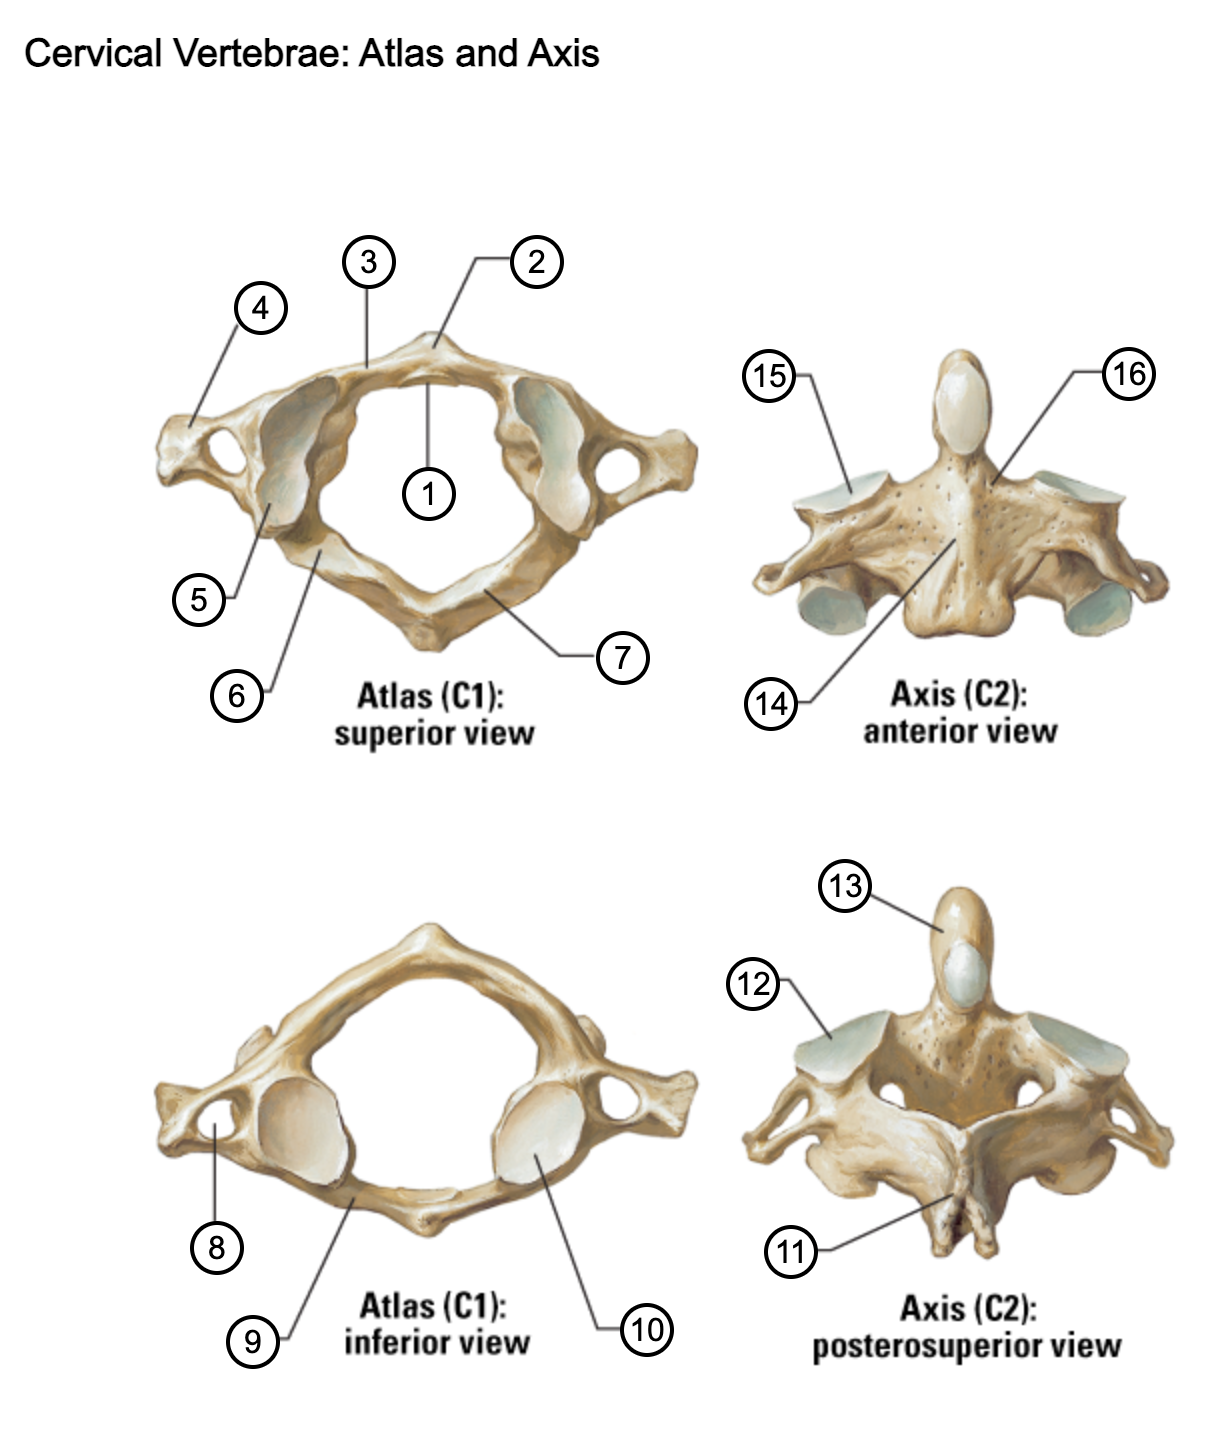

1

facet for dens

2

anterior tubercle

3

anterior arch

4

transverse process

5

superior articular surface of atlas

6

groove for vertebral artery

7

posterior arch

8

transverse foramen

9

anterior arch

10

inferior articular surface of atlas

11

spinous process

12

superior articular facet

13

dens of axis

14

body of axis

15

superior articular facet for atlas

16

pedicle of vertebral arch